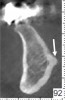

Mandibular Structures Mandibular Foramen and Lingula

One of the first landmarks noticed in the posterior mandible is the mandibular foramen. At this site, the inferior alveolar nerve enters the ramus (Figure 1). When administering a mandibular block injection, it is often advisable to insert the needle 6 mm to 10 mm above the occlusal plane,5 because the mandibular canal is coronal to the occlusal plane 2% to 25% of the time.6,7 Therefore, an injection at the occlusal plane may result in failure to attain a good anesthetic result. The ridge superior to the foramen is the lingula, and the sphenomandibular ligament inserts at this location (Figure 1).